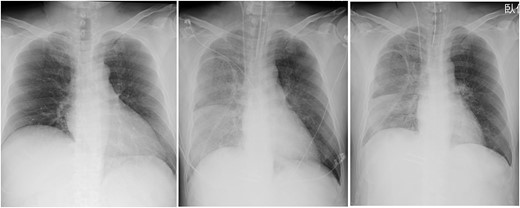

Post-operative CXR showed unilateral consolidation (Fig. 2). Re-expansion pulmonary edema was suspected. Mechanical ventilation with a high PEEP of 12–14 cmH2O and a peak inspiratory pressure of 30 cmH2O was provided; nonetheless, there was no improvement in the respiratory condition, resulting in hypercapnia and severe acidosis with a pH of 7.06 and pCO2 of 94.4 mmHg. Thus, VV-ECMO was immediately initiated after placing a 21 Fr drainage cannula in the right atrium through the right femoral vein and a 15 Fr return cannula through the left femoral vein under fluoroscopic guidance. Unfractionated heparin was used for anticoagulation with a target ACT of 150 s, while being concerned about the risk of bleeding from the surgical site.

Chest radiographs obtained pre-operation (left), post-operation (middle) and 2 days post-operatively (right).

Two days post-operatively, VV-ECMO was terminated due to improvement in respiratory function, hypercapnia and acidosis. The amount of sputum also decreased remarkably with PEEP at 12 cmH2O. The ECMO duration was 41 h. Mechanical ventilatory support was terminated on POD 9. The patient was discharged on POD 48.